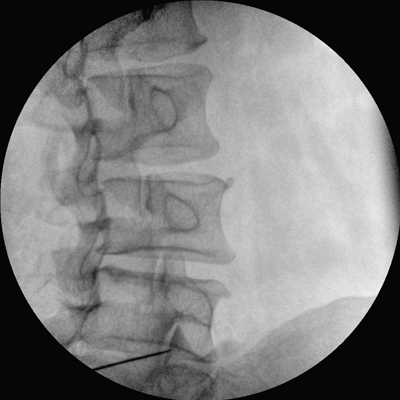

四維電動(dòng)運(yùn)動(dòng)控制,平滑定位,使得復(fù)雜角度快速實(shí)現(xiàn)。

專業(yè)的圖像處理系統(tǒng),為您提供高分辨率、高灰階圖像。